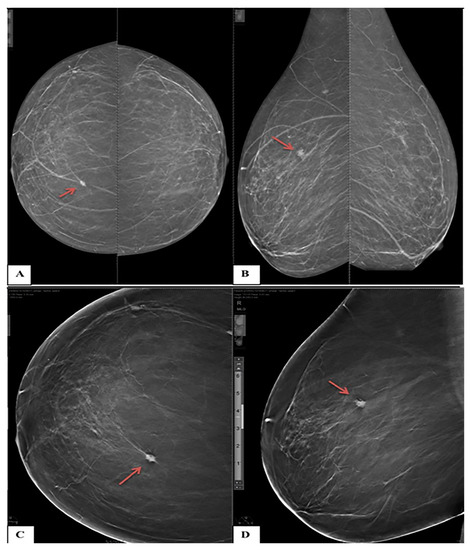

Figure 4. A 40-year-old female presented with bilateral breast lumps. (A) Mediolateral oblique and (B) Craniocaudal DM images of both breasts show heterogeneous dense breasts (ACR C) with left breast retroareolar, right breast retroareolar, and right breast lower inner quadrant dense lesions with obscured margins (arrows). No microcalcifications or speculated masses. (C) Mediolateral oblique and (D) Craniocaudal DBT images show more margin characterizations of the lesions, which are medium-dense, well-defined rounded lesions with smooth margins and a characteristic halo sign (arrowheads). The lesions were classified as BI-RADS 3 according to DM and BI-RADS 2 according to DBT. Histopathological examination revealed simple cysts.